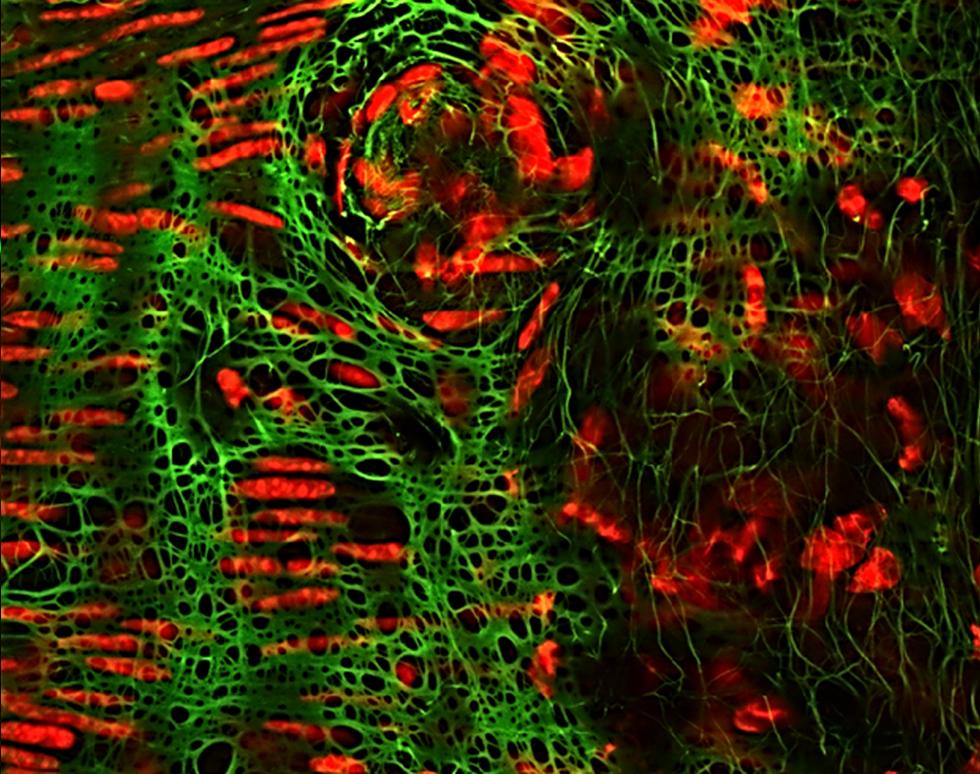

Retina - Jessica Teeling